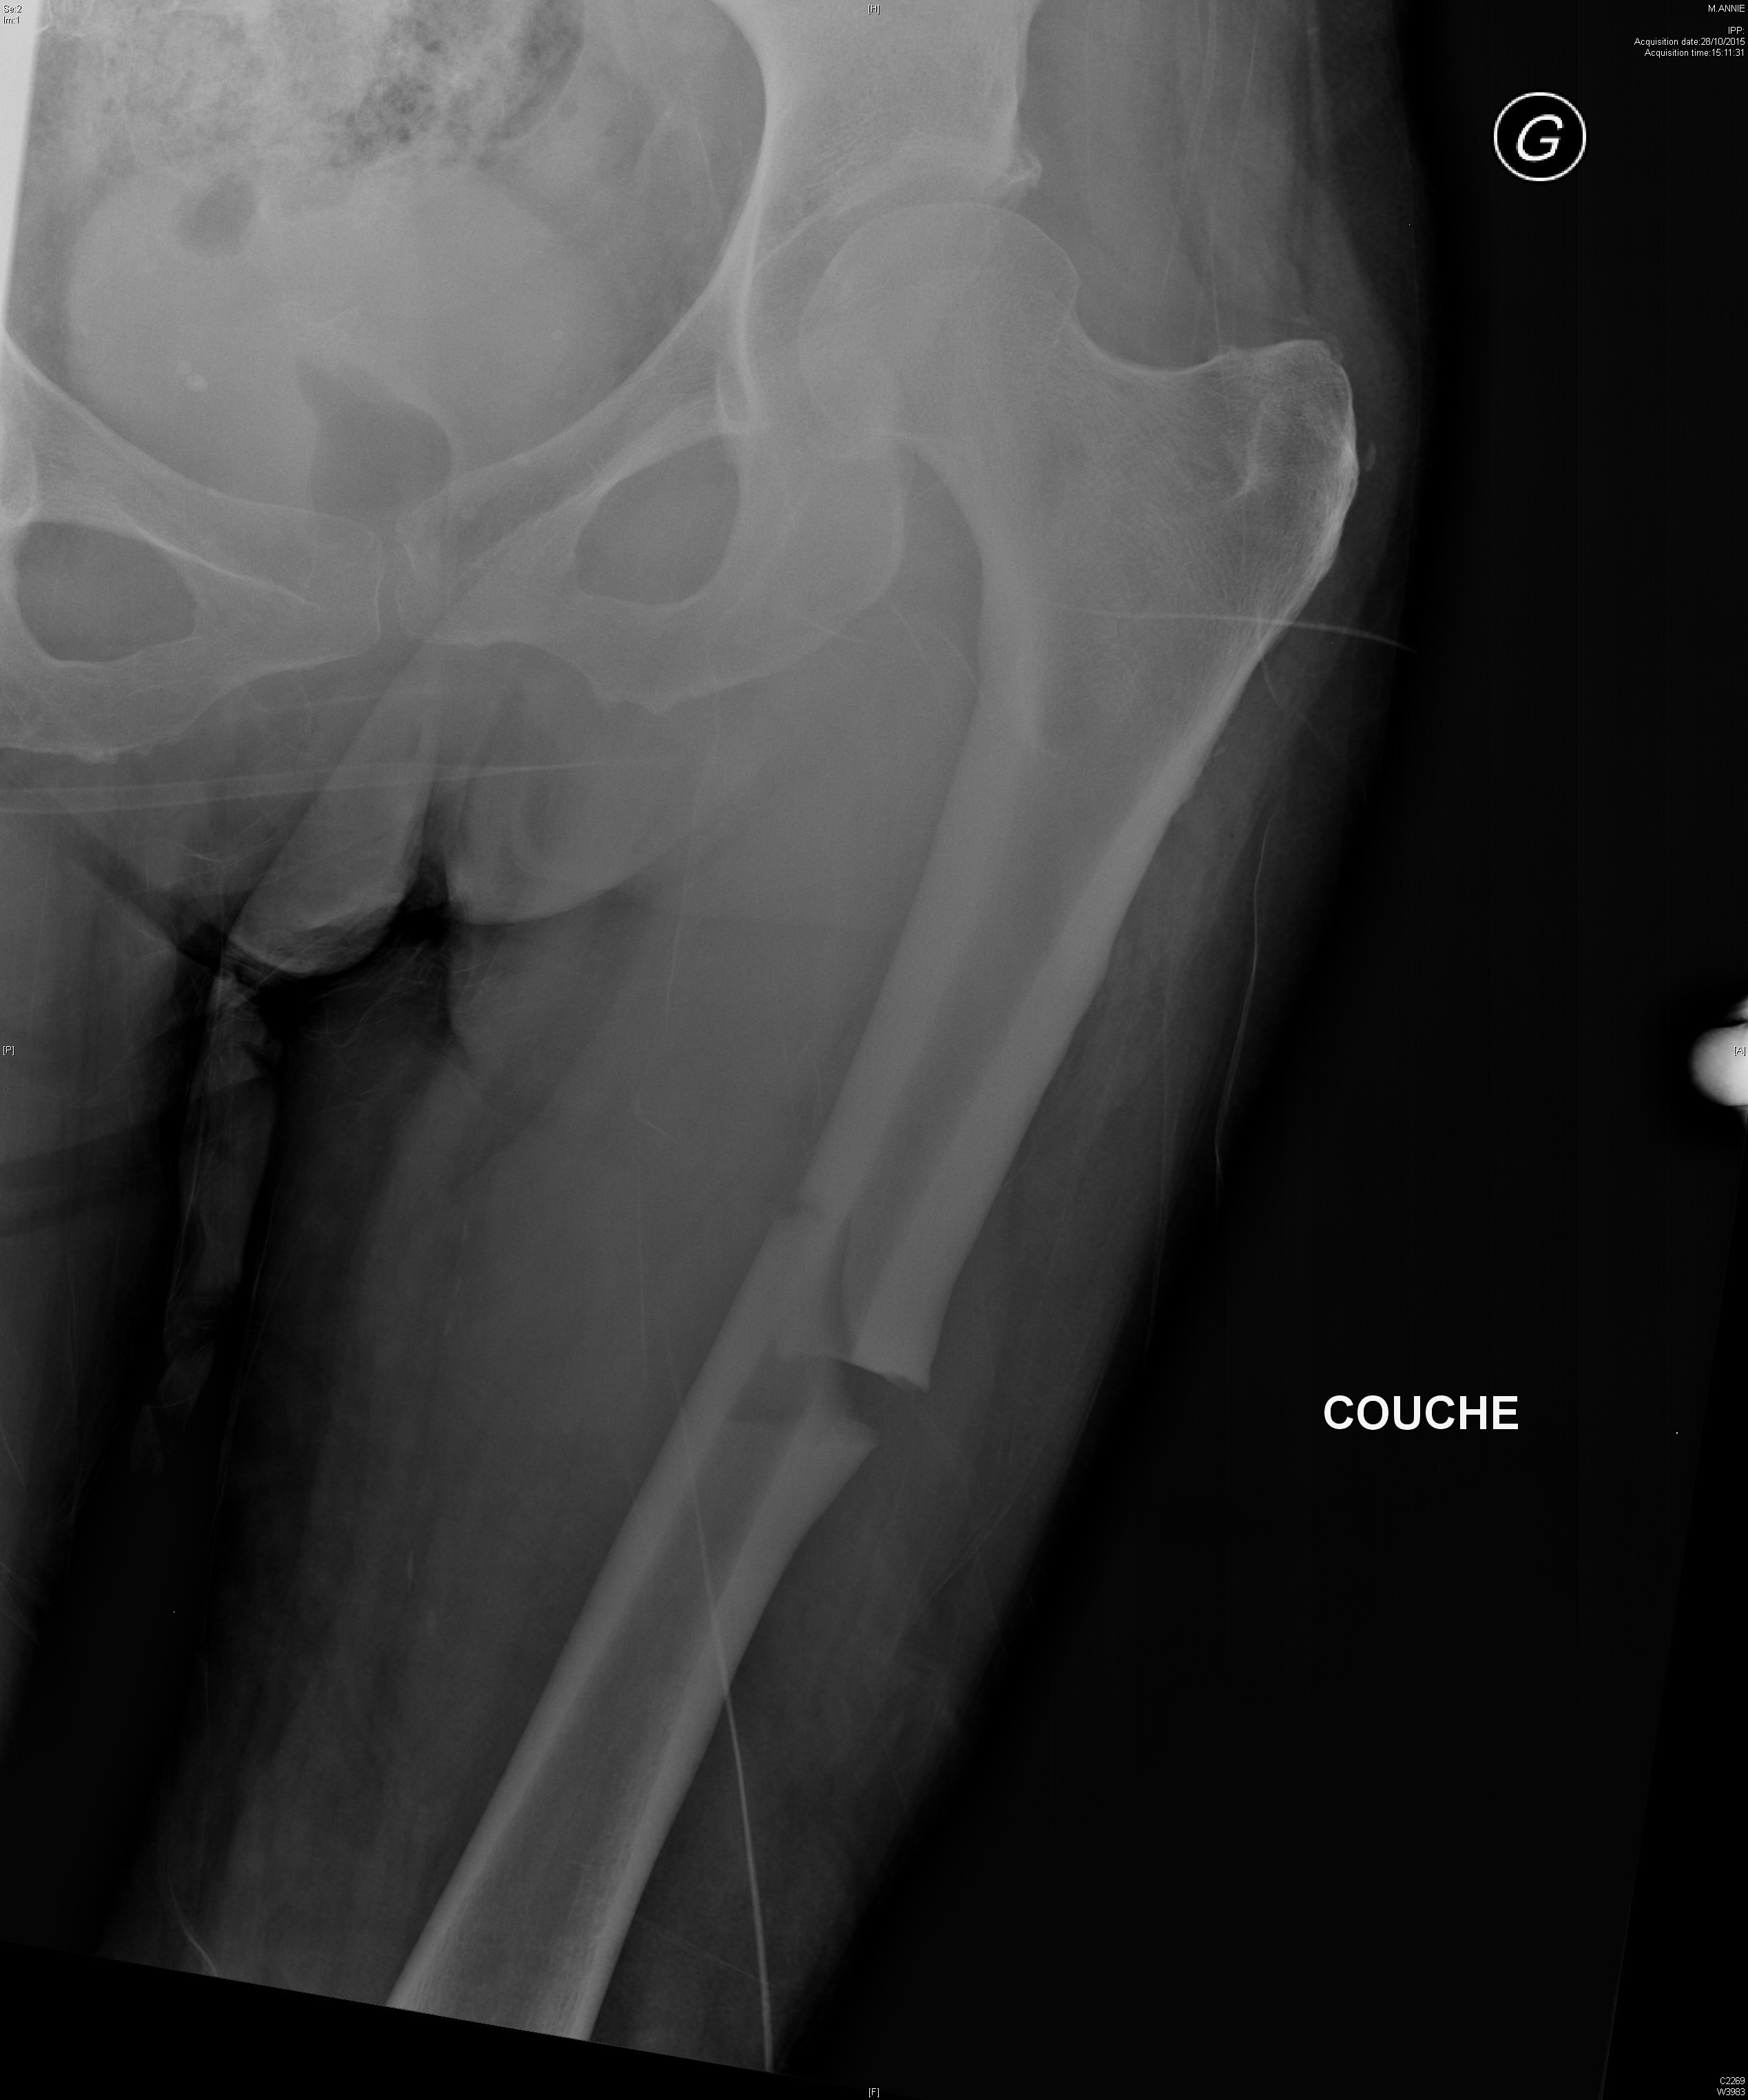

Coxite rapidement destructrice avec ostéonecrose chez une patiente traitée dans le cadre d'un syndrome des anti-synthétases

Dysplasie fibreuse du fémur gauche dans un contexte de dysplasie fibreuse polyostotique

Fracture fémorale atypique sous biphosphonates

Radiographie retrouvant une dysplasie acétabulaire bilatérale ainsi qu'une lésion de dysplasie fibreuse du col fémoral droit chez une jeune fille